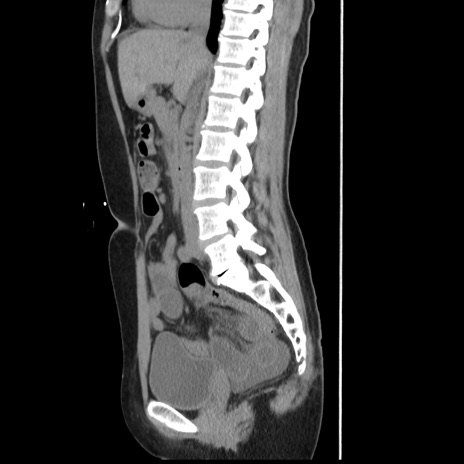

症例10(矢状断像)

横断像

冠状断像